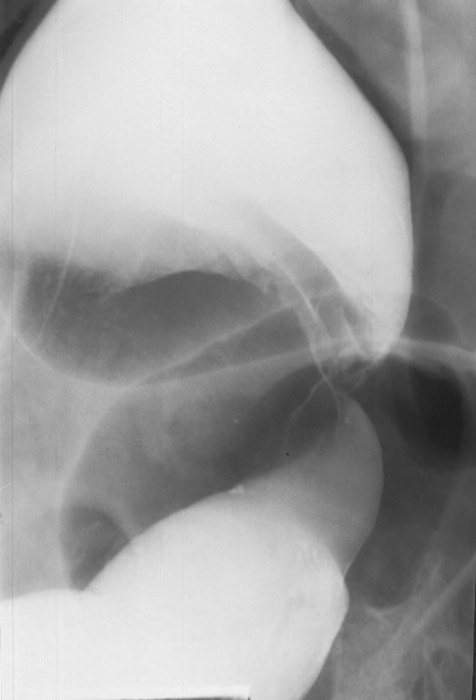

In the cecum and sigmoid colon. (image shows cecal volvulvus)

How does cecal volvulus occur?

The cecum twists on its long axis and often displaces upward and to the left.